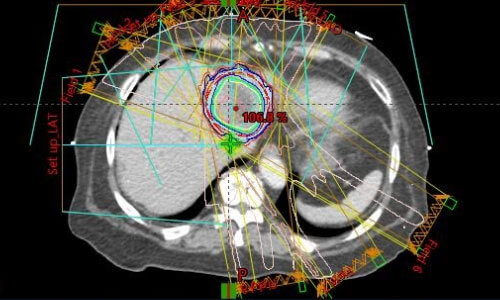

세 번째로, 영상 촬영을 통해 치료 계획을 수립합니다. 모의 치료 과정에서는 CT나 MRI와 같은 영상 진단 장비를 사용하여, 암 및 주변 조직의 정확한 위치를 파악합니다. 이 정보는 방사선 치루의 정밀한 계획을 수립하는 데 필수적입니다.

네 번째로, 치료계획을 최적화합니다. 얻어진 영상 정보를 기반으로 의료팀은 방사선의 최적 조사 각도, 선량, 그리고 치료 기간 등을 결정합니다. 고급 컴퓨터 소프트웨어를 활용하여 방사선이 암 조직에만 정확히 도달하도록 계획을 세우며, 건강한 조직에 미치는 영향을 최소화하기 위해 다양한 시뮬레이션을 수행합니다.